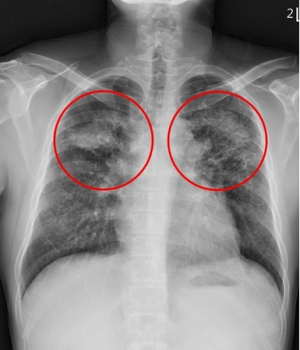

勞動部職安署、職業災害預防及重建中心、環境職業醫學會聯合各地職業傷病診治專責醫院進行人造石產業暴露危害與健康風險調查,其中,花蓮慈濟醫院於2023年底具出相關報告,顯示人造石矽肺症有年輕化及病程發展迅速的現象。花蓮慈院胸腔內科劉迪塑醫師指出,由於矽肺症屬於不可逆的吸入性肺部疾病,且即便病人停止暴露在粉塵環境裡,病程仍然會持續進展,因此預防的重要性不可忽視,呼籲相關從業者應多加注意!